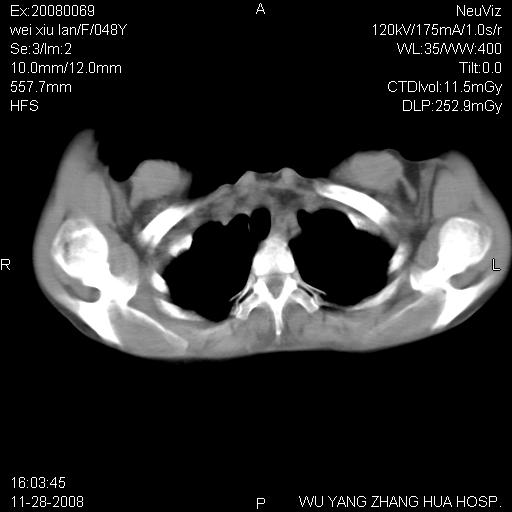

标题: CT16847:女,48岁,咳嗽,发热两日,平常偶有上腹部不适。 [打印本页]

标题: CT16847:女,48岁,咳嗽,发热两日,平常偶有上腹部不适。

支持左侧膈疝,心脏受压右移.

胃、脾脏及部分肠管明显升高,并压迫心脏移位,

首先考虑:左侧膈疝。

左侧胸腔内见胃肠及脾脏影

支持膈疝